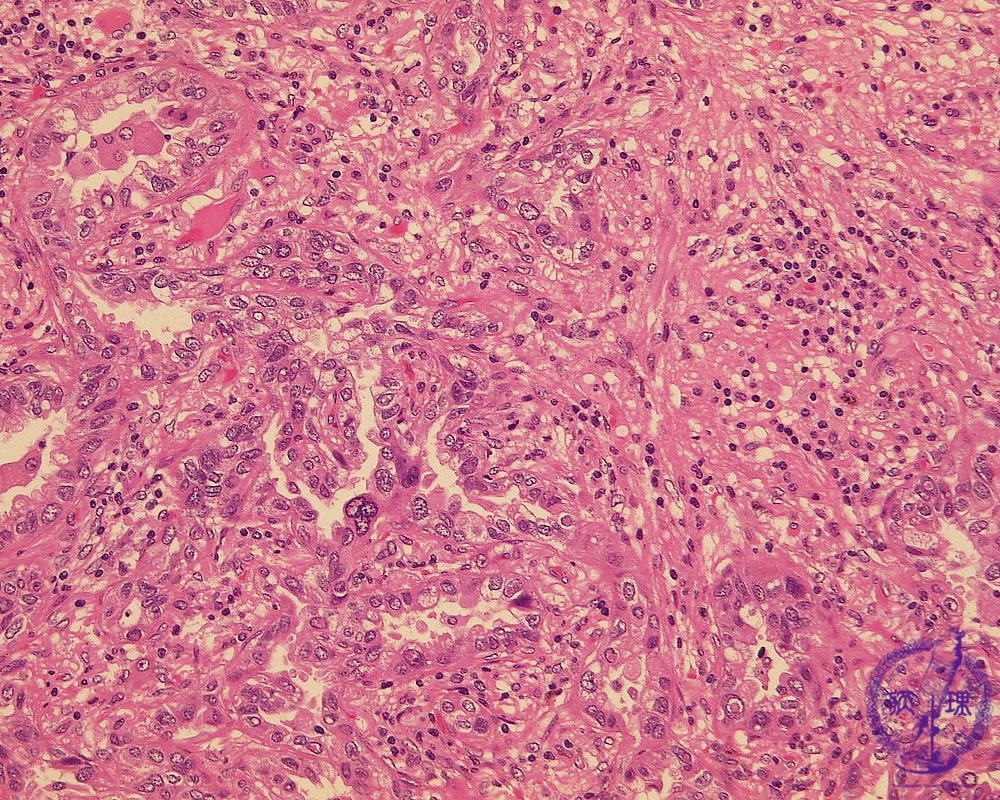

- ★(17)Non-small cell lung carcinoma(adenocarcinoma)

Microscopic view (HE stain, high power view): Adenocarcinoma of lung. Centrally within the carcinoma, tumor cells form irregular tubules and proliferate by invasion. There is a predominantly lymphocytic infiltrate within the complex, intricate stroma.